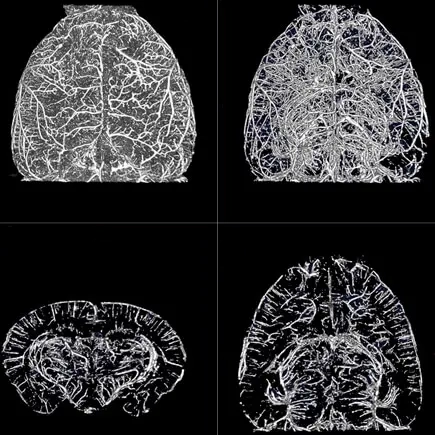

Metastaza nowotworu, znakowanie bioluminescencyjne: IVIS Spectrum CT